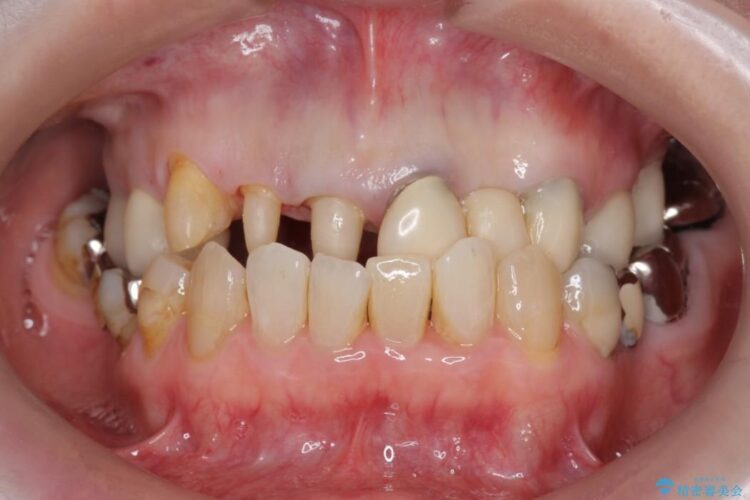

上顎右側の前歯2本のかぶせ物部分の再治療と犬歯に発生していた虫歯治療を主訴に来院されました。

前歯のかぶせ物に関しましては、内面が金属で覆われているため歯茎にその色が透けて見えるという審美的な問題と、かぶせ物と歯の境界が不適合であるという問題がありました。

犬歯の虫歯につきましては、何度も詰め物治療が繰り返されている痕跡があり今回虫歯を取りきるにあたり歯の強度に不安が残るため前歯と同時にかぶせ物の治療をしていくことを計画しました。

今回の症例では金属の色が透けていることを気にされていたので、土台から金属を除去し、金属を使用していないオールセラミックのかぶせ物を使用することとしました。